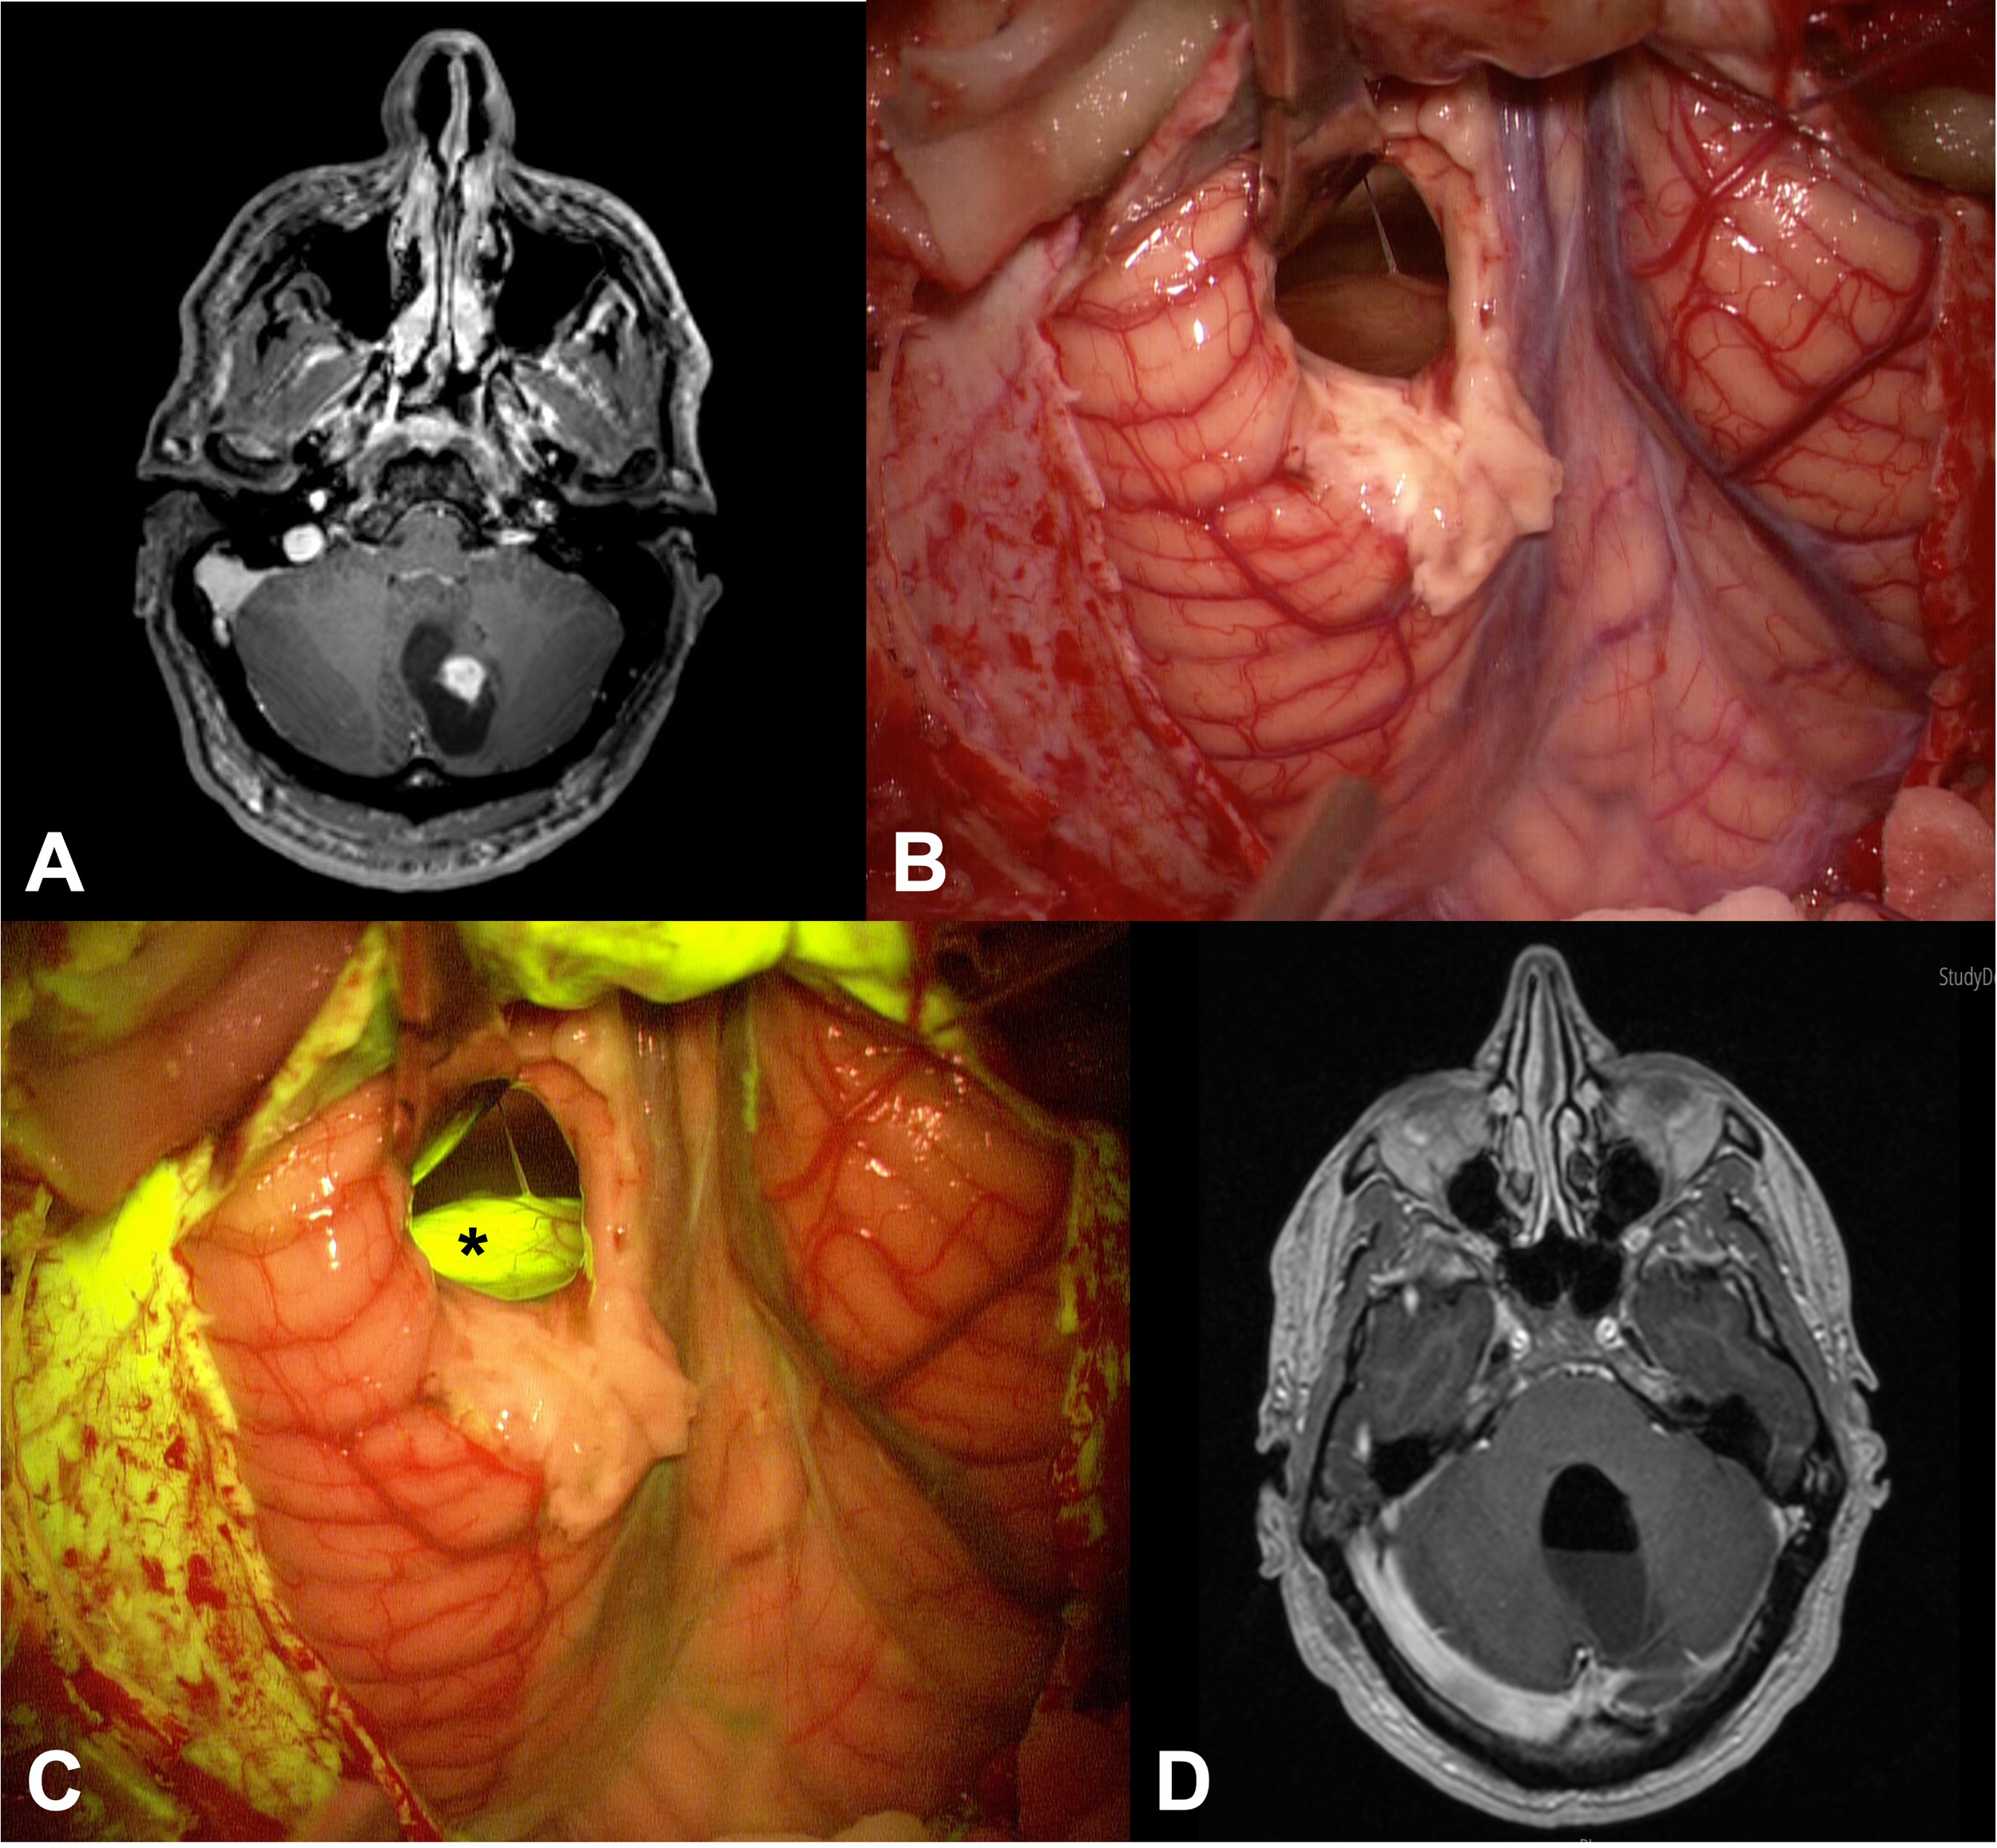

All the patients presented with variable contrast enhancement patterns in the preoperative MRI: PAs mostly showed a solid, highly enhancing component (the mural nodule) with a large cyst (Figure 1); furthermore, several other contrast enhancement patterns were observed, such as homogeneous and intense contrast uptake or peripheral, heterogeneous contrast enhancement with central cystic-necrotic areas (Figure 2).

Figure 1

(A) Preoperative axial post-contrast T1 MRI of patient n.26 showed a left cerebellar lesion with its enhancing solid component and a large cystic component. (B, C) Intraoperative images: after cystic distension through a small corticectomy, the solid part of the tumor was exposed (B), appearing as a greyish tissue; this tissue appeared more evident when the YELLOW 560 filter was activated (asterisk in (C)), as a bright and intense fluorescence. (D) Postoperative axial post-contrast T1 MRI demonstrated complete tumor removal of the lesion.